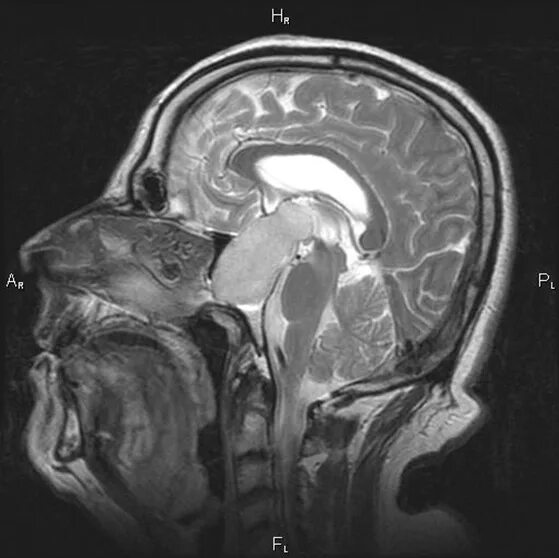

После кт через сколько можно делать мрт